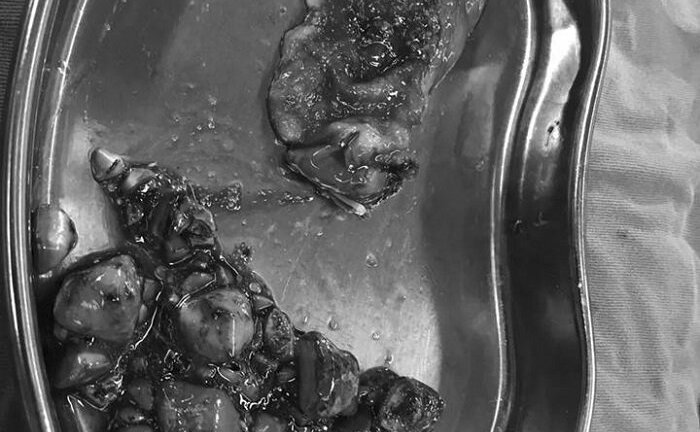

Ăn nhiều mỳ tôm và đồ ăn sẵn, cô gái bị kết 100 viên sỏi trong túi mật

Thông tin một cô gái mới 20 tuổi đã bị 100 viên sỏi mật, chỉ vì liên quan đến món ăn cô yêu thích, đang là lời cảnh báo cho tất cả mọi người.